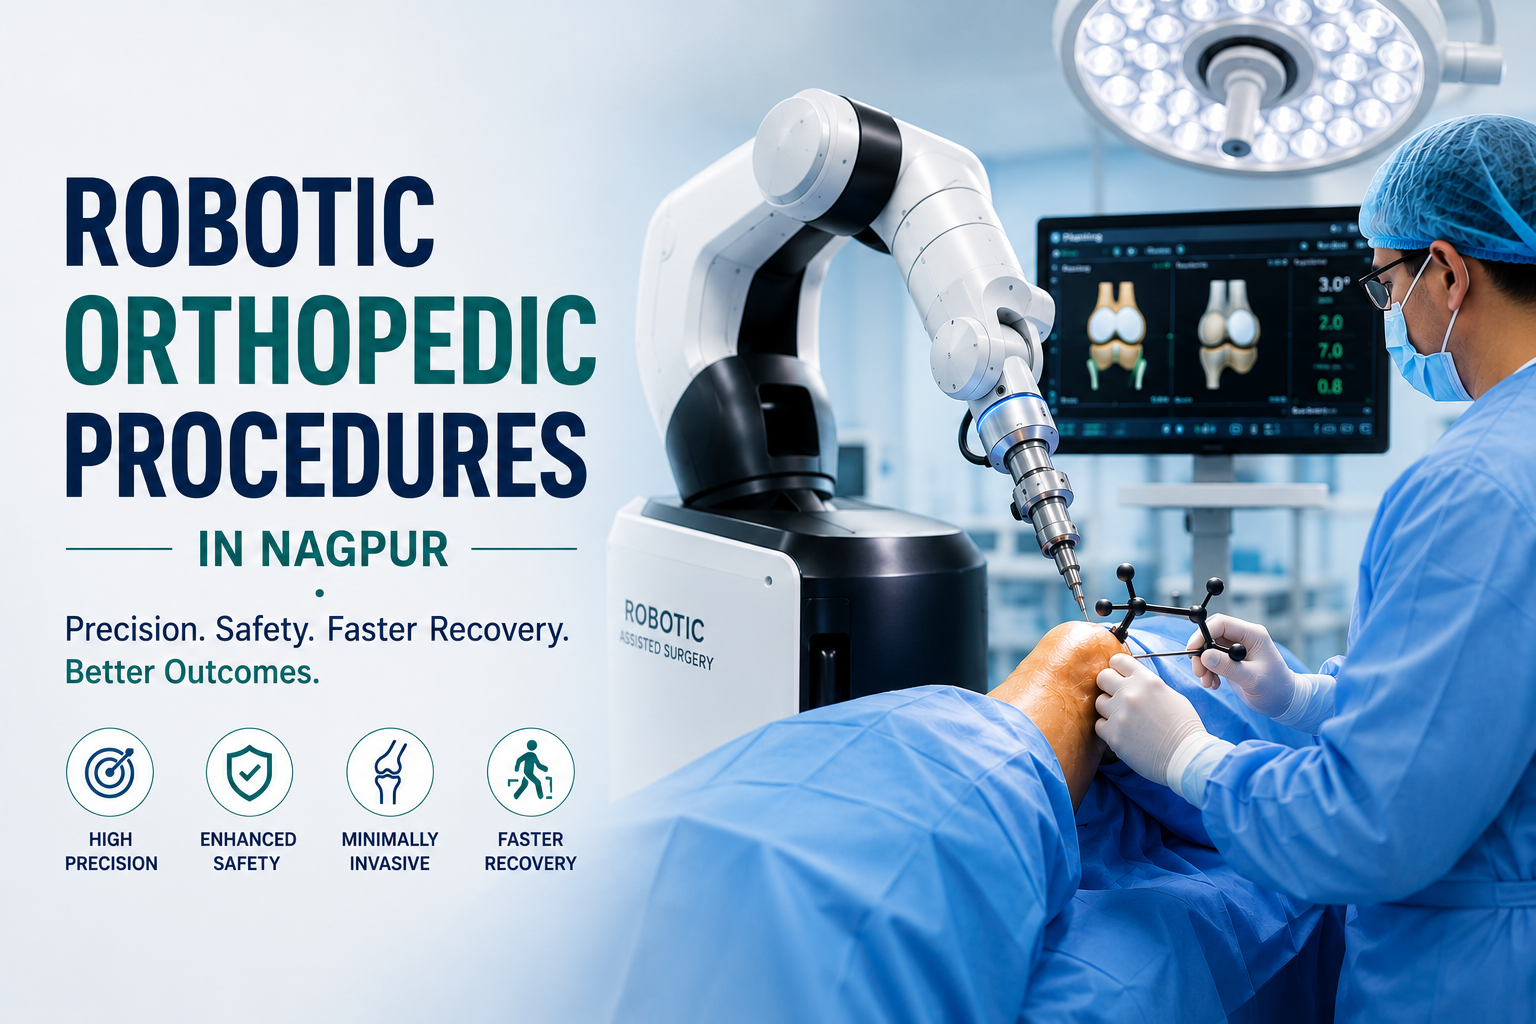

Robotic Orthopedic Procedures In Nagpur – Dr. Abhishek Bhalotia Understanding …

Introduction: Why Robotic Assisted Surgery in Korea Is Redefining Modern …

Introduction: Why Robotic Orthopedic Surgery in Korea Is Transforming Modern …